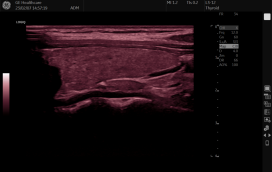

频率(Frequency) 4 F% \1 G- ^4 |3 A7 l

在成人超声心动图检查中,频率范围2~5 MHz。高的频率可提高图像的分辨率,但穿透力不足。操作者应从高到低逐渐调节,以满足声波穿透力的需求。检查中应使用可能达到的最高频率来取样。 1 C4 U+ O7 u9 Y* o, K* d

谐波(CHI/CH/THI/Harmonics) 4 Q& a" P- D& v* l) J# L# |

谐波是利用高于基波频率数倍的返回频率来形成超声图像。谐波频率是由声束穿过组织时变形扭曲而产生。谐波取样大多普遍使用二次谐波频率,它是基波频率的两倍。对于过度肥胖者和肌肉组织密集的患者具有特殊帮助,可以获取信噪比最大化情况下更加清晰的图像。心脏超声应使用二次谐波以得到高质量图像。 1 K( q8 h( ~' }! q* I0 r